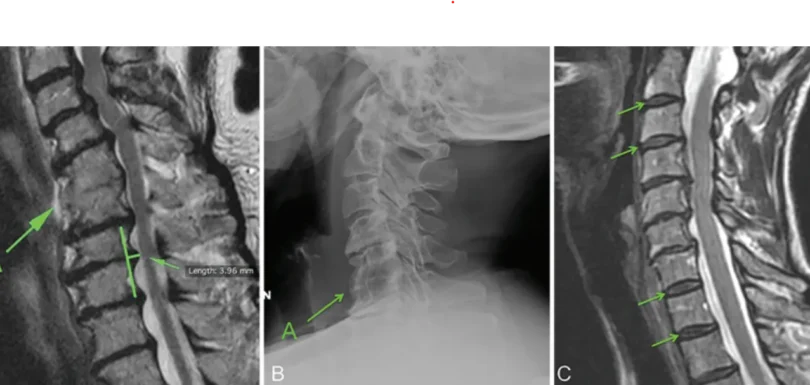

Cervical / Lumbar Disc Disease

Dr. Muhammad Aqeel Natt offers advanced diagnosis and treatment for lumbar disc disease, herniated discs, and lower back pain at The Brain and Spine Centre. Restoring mobility and comfort through expert spine surgery.